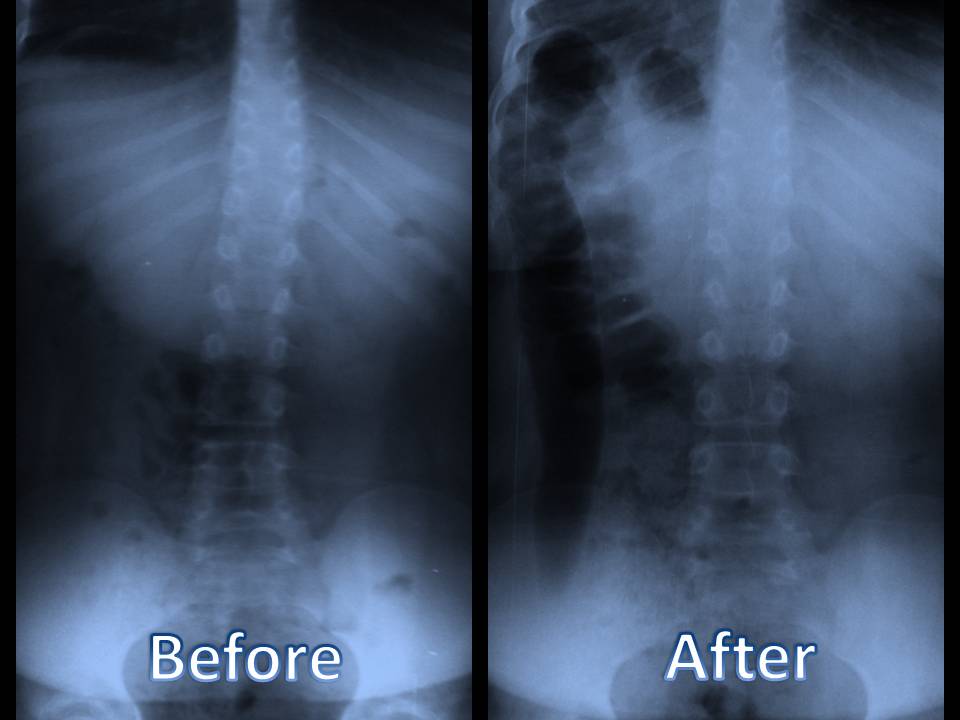

Studji dwar l-Immaġini

L-immaġini f'mard deġenerattiv tad-diska tintuża prinċipalment biex tiddeskrivi relazzjonijiet anatomiċi u karatteristiċi morfoloġiċi tad-diski affettwati, li għandha valur terapewtiku kbir fit-teħid ta 'deċiżjonijiet futuri għal għażliet ta' trattament. Kwalunkwe metodu ta 'immaġini, bħal radjografija sempliċi, CT, jew MRI, jista' jipprovdi informazzjoni utli. Madankollu, kawża sottostanti tista 'tinstab biss fi 15% tal-pazjenti billi l-ebda bidliet radjoloġiċi ċari ma huma viżibbli f'mard deġenerattiv tad-diska fin-nuqqas ta' ħernja tad-diska u defiċit newroloġiku. Barra minn hekk, m'hemm l-ebda korrelazzjoni bejn il-bidliet anatomiċi li dehru fuq l-immaġini u s-severità tas-sintomi, għalkemm hemm korrelazzjonijiet bejn in-numru ta 'osteofiti u s-severità ta' uġigħ fid-dahar. Bidliet deġenerattivi fir-radjografija jistgħu jidhru wkoll f'nies bla sintomi li jwasslu għal diffikultà biex jikkonformaw ir-rilevanza klinika u meta tibda l-kura. ("Marda tad-Diska Deġenerattiva" Fiżjopedja)

Trattament kirurġiku

It-trattament kirurġiku huwa riservat għal pazjenti bi terapija konservattiva falluta b'kont meħud tas-severità tal-marda, l-età, komorbidità oħra, kundizzjoni soċjo-ekonomika, u l-livell ta 'riżultat mistenni. Huwa stmat li madwar 5% tal-pazjenti b'mard deġenerattiv tad-diska jgħaddu minn operazzjoni, jew għall-marda tal-ġenbejn tagħhom jew għall-marda ċervikali. (Rydevik, Bjärn L.)

Proċeduri ta 'l-Ispina Lumbari

Il-kirurġija tal-ġenbejn hija indikata f'pazjenti b'uġigħ qawwi, b'tul ta '6 sa 12-il xahar ta' terapija tal-mediċina ineffettiva, li għandhom stenożi kritika tas-sinsla. Il-kirurġija ġeneralment hija proċedura elettiva ħlief fil-każ tas-sindrome ta 'cauda equina. Hemm żewġ tipi ta 'proċeduri li għandhom l-għan li jinvolvu fużjoni spinali jew dekompressjoni jew it-tnejn. ("Marda tad-Diska Deġenerattiva: Sfond, Anatomija, Patofiżjoloġija.")

Fużjoni spinali tinvolvi li twaqqaf movimenti fuq segment vertebrali bl-uġigħ sabiex tnaqqas l-uġigħ billi tgħaqqad diversi vertebri flimkien billi tuża tilqim tal-għadam. Huwa meqjus effettiv fuq medda twila ta 'żmien għal pazjenti b'mard deġenerattiv tad-diska li għandhom malalinament spinali jew moviment eċċessiv. Hemm bosta approċċi għall-kirurġija tal-fużjoni. (Gupta, Vijay Kumar, et al)